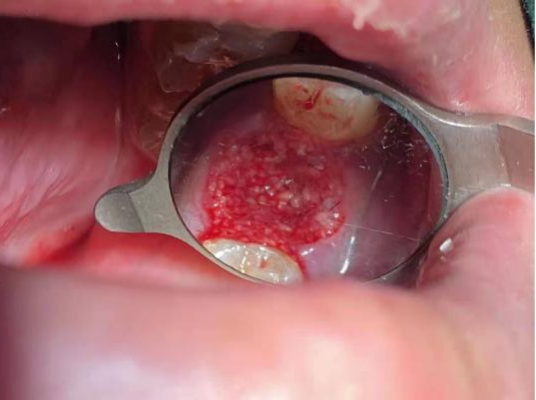

填骨